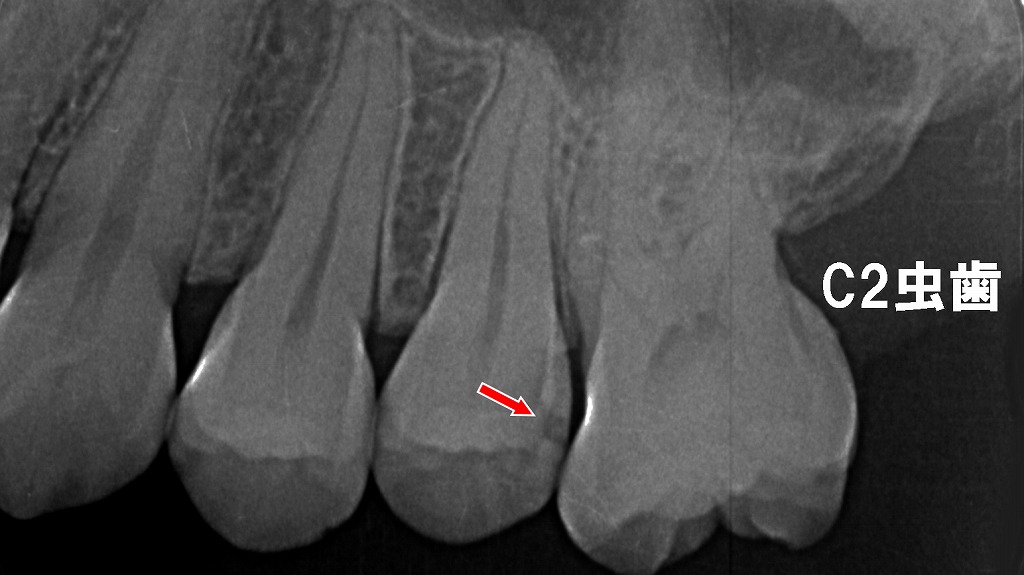

レントゲン画像では、肉眼では見つけにくい歯と歯の間の虫歯(C2)が明確に確認できます。赤矢印の部分は上顎5番遠心に生じた象牙質まで進行した虫歯で、痛みが出る前に発見するためにはレントゲン検査が有効です。早期診断により、神経を残すための最小限の治療が可能になります。